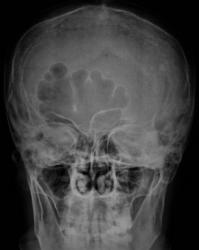

Представлены, на диске, такие изображения черепа. Что посоветуете уважаемые коллеги?

Уважаемый  Валентин Львович, я так понимаю Вас смущает ячейки лобной пазухи? В данном случае надо обратить внимание на толщину костей крыши черепа, а следовательно и на турецкое седло, следует проконсультироваться у эндокринолога с дальнейшим проведением МР-исследования гипофиза.

Кости свода толстоваты, пазухи крупные. Турецкое седло не изменено. По-моему, стоит беспокоиться, только если есть эндокринные нарушения.